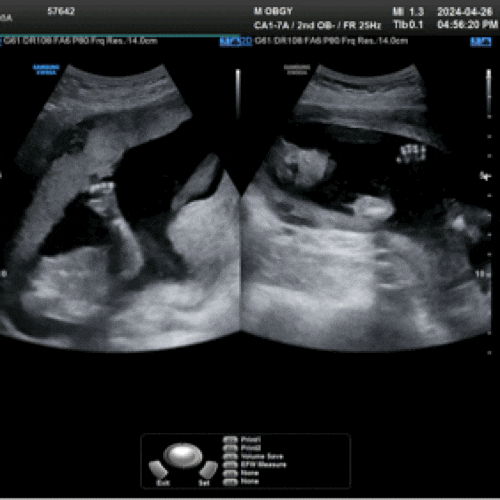

임신일기#7 장군감 딸래미가 될 관상인가,, 임신후기는 힘들어 (29~31주차)

29주차 태동이 정말 정말 격해진 아가씨 자다가도 퍽퍽 점심시간이고 새벽이고 시간을 안가리고 움직이는,,...

임신일기#7 새로운 증상 등장! 비문증, 이관개방증 그리고 활발해진 태동(25~28주차)

25주차 이제 정말 배가 많이 나와서 뭘해도 배가 거슬리는 지경이 됐다 설거지나 요리를 해도 배가 씽크대...

임신일기#5 다사다난했던 임신 중기 본격적인 태동시작(17~19주차)

잘먹고 잘자는 임신 중기 오히려 난 초기때보다 중기에 잠이 미친듯이 온다,, 4시 퇴근 후 잠자고 일어나서...